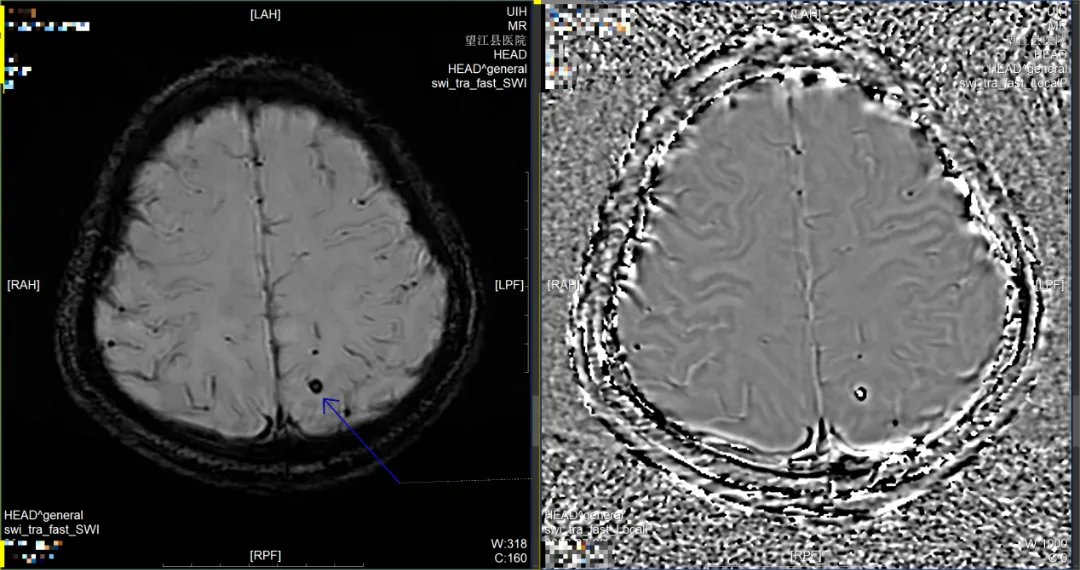

2.SWI(磁敏感加權(quán)成像):鎖定毫米級微出血,預(yù)警腦血管病變。

腦微出血是高血壓、淀粉樣血管病甚至早期阿爾茨海默病的敏感標(biāo)志物,但常規(guī)CT/MRI難以檢出。SWI技術(shù)對順磁性物質(zhì)(如出血產(chǎn)物)的敏感性是常規(guī)序列的5倍,可發(fā)現(xiàn)小至1mm的微出血灶。這些“紅色警報(bào)”能提示血管脆性改變,幫助評估卒中風(fēng)險(xiǎn),指導(dǎo)生活方式調(diào)整和藥物干預(yù)。

左側(cè)頂葉微出血灶